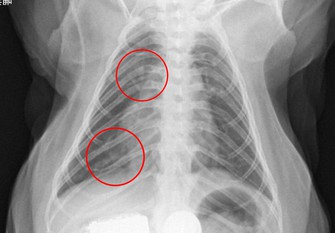

チームによると、5~6月、カニクイザル3匹の鼻や口にウイルスが溶けた液体を垂らして症状を観察。3匹ともウイルスを垂らした翌日に発熱し、1匹はレントゲン検査で肺炎の症状が見られた。いずれも軽症で、約10日後に回復した。